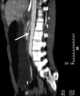

Superior mesenteric artery (SMA) syndrome is a gastro-vascular disorder in which the third and final portion of the duodenum is compressed between the abdominal aorta (AA) and the overlying superior mesenteric artery. This rare, potentially life-threatening syndrome is typically caused by an angle of 6°–25° between the AA and the SMA, in comparison to the normal range of 38°–56°, due to a lack of retroperitoneal and visceral fat (mesenteric fat). [Source: Wikipedia ]